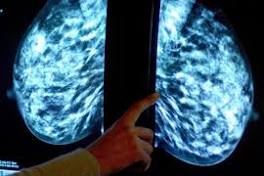

Could a Massive Data Dump Help Solve Breast Cancer? When a breast cancer patient goes in for genomic testing, data usually gets locked ... doctors, or patients can seek out genetic patterns in cancer data.

Study Refines the Risk for Breast Cancer Recurrence BOSTON — The risk for local recurrence of breast cancer decreases as event-free survival lengthens, according to an analysis of a large database ...

Nancy Reagan's breast cancer and her lasting contribution to women's health Mrs. Reagan was a breast cancer survivor and like fellow First Lady and survivor Betty Ford decided to share her diagnosis and treatment publicly to ...

Rita Wilson Advocates for Second Opinion After Battling Breast Cancer: 'I Just Had That Gut' Feeling Now "one hundred percent healthy!" after undergoing a double mastectomy following her breast cancer diagnosis, Rita Wilson is urging women to ...

| Breast Cancer Facts Breast Cancer Facts: did you know that... Every 13 minutes, a woman dies from breast cancer in the U.S?

| UNRWA raises awareness about breast cancer and the importance of early detection among ... As part of its Breast Cancer Awareness Campaign, UNRWA is organizing over 100 awareness and outreach sessions throughout the Gaza Strip.

| Breast cancer in pregnant women and young mothers: new survey A new survey has shown that 1 in 10 younger women with breast cancer notice their first symptom during pregnancy or when breastfeeding.

| Breast Cancer Support Group - March This group meets on the ground floor of Hahne Regional Cancer Center, 100 Hospital Ave., DuBois. All breast cancer survivors at any stage – newly ...

| Breast cancer screening for women at average risk Breast cancer screening for women at average risk: 2015 guideline update from the American Cancer Society.